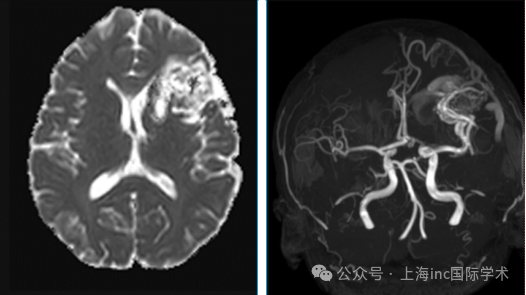

1. 初筛利器:磁共振(MRI)

像给大脑拍"高清写真",能够清楚地显示动静脉分流和病灶周围脑实质的结构。MRA 上可以看到不同程度扩张的供血动脉,有时可以在供血动脉上发现动脉瘤的存在。同时 MRI 也是发现既往出血的方法。

2. 金标准检查:脑血管造影(DSA)

为AVM血管形态的分析,可以明确供血动脉的数量和来源,以及发现血流相关性动脉瘤。